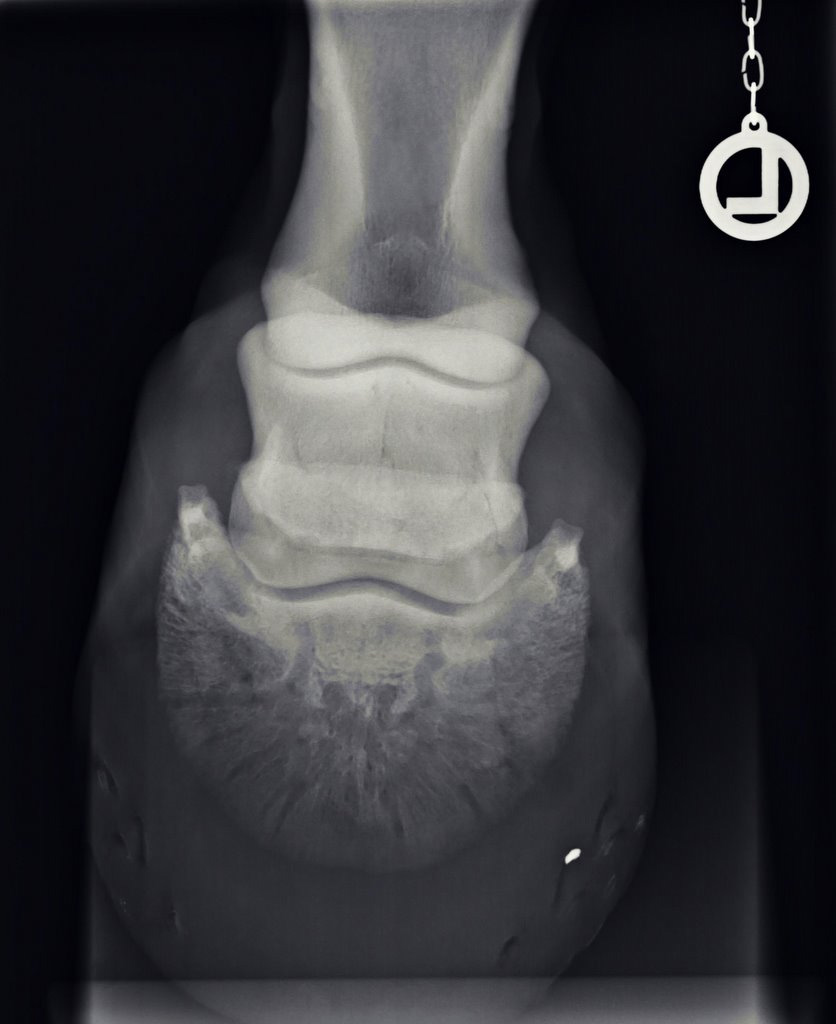

Illustrative Mindeststandardaufnahmen zur Beurteilung nach dem Röntgenleitfaden: